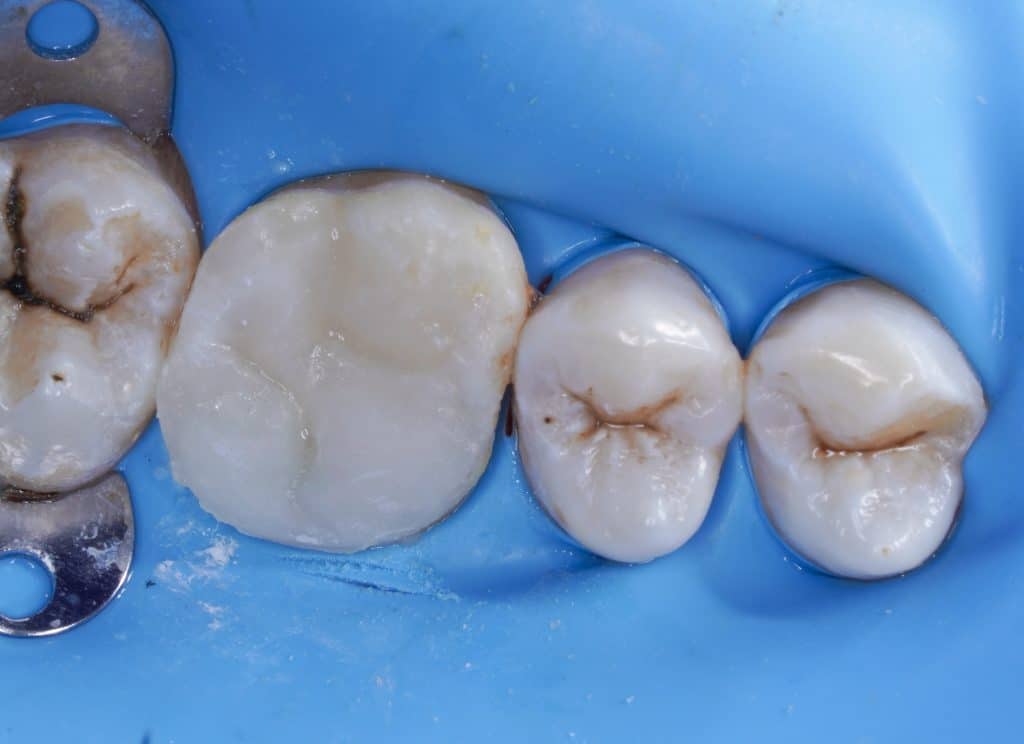

UL6 with SAP and deep palatal caries.

Caries removal and cleaning to determine the margin height then margin elevation as a pre endo build up under rubber dam isolation, endodontic treatment in the same visit to minimize flar up and direct restoration was done in the second visit.